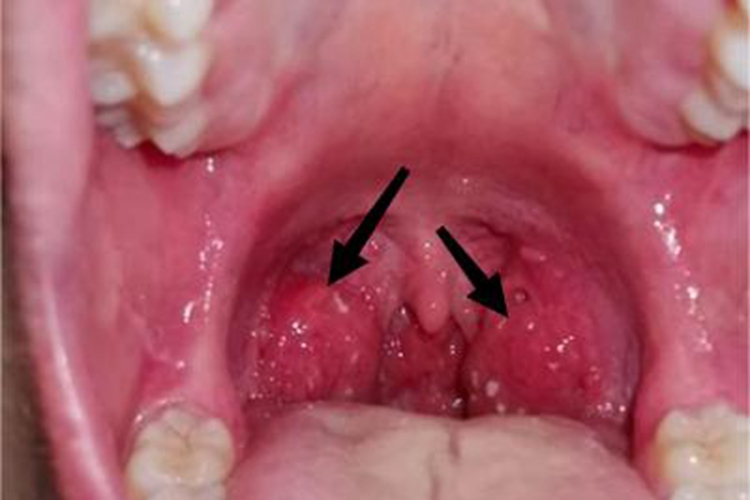

淋菌性咽炎可见受累部位出现充血表现,表面可有白色脓点,患者可有疼痛感。

淋菌性咽炎发生时,可导致病损部位充血、肿胀,表面出现白色脓点、脓片,肿胀严重时可超出双侧扁桃体弓范围,可能伴随出血、流脓等情况,患者可有疼痛感。